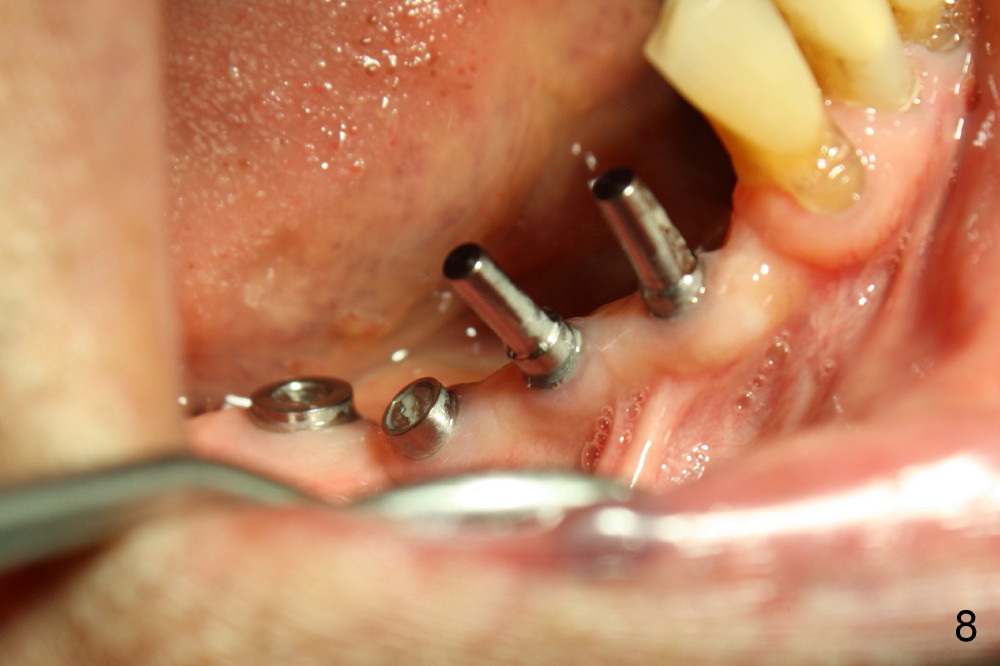

Two weeks later, two of one piece implants are placed at the site of #3 and 4 (3x17), regular two piece implant at #5 (3.5x11; Fig.6).  Fig.7 is taken one week post op.

Four months after implantation, the gingiva around these four implants is healthy (Fig.8).  Healing cuffs are placed over the implants #5 and 6 (Fig.9).  The trajectory for the one piece implants is within normal limit relative to the opposing dentition (Fig.9,10).